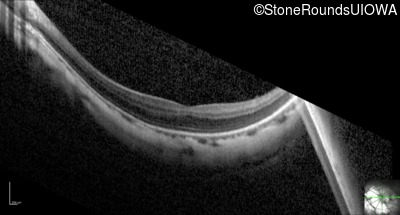

Optical Coherence Tomography - Right - 20/25 -1

Exemplar / OCT Stack

OCT Stack